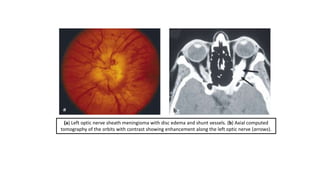

(a) Left optic nerve sheath meningioma with disc edema and shunt vessels. (b) Axial computed

tomography of the orbits with contrast showing enhancement along the left optic nerve (arrows).

(a) Left opticnerve sheath meningioma with disc edema and shunt vessels. (b) Axial computed tomography of the orbits with contrast showing enhancement along the left optic nerve (arrows).